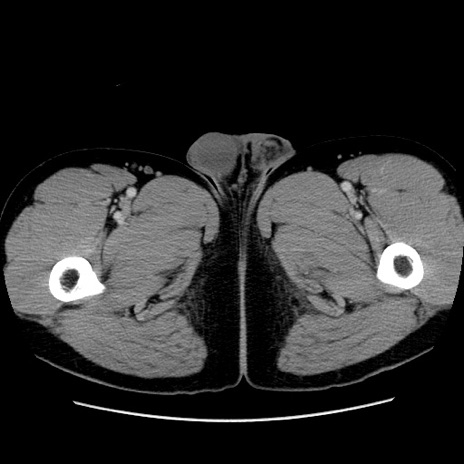

冠状断像

【症例】30歳代男性

【主訴】腹痛、嘔吐

【現病歴】昨晩から突然の腹痛あり、その後嘔吐、軟便も出現。腹痛が改善しないため救急搬送となる。2日前にしめ鯖の食事歴あり。

【身体所見】意識清明、苦悶様、BP 135/90mmHg、BT 35.7℃、腹部:平坦、やや硬、心窩部〜臍部に自発痛、圧痛あり、筋性防御+、反跳痛-

【データ】WBC 8100、CRP 0.57